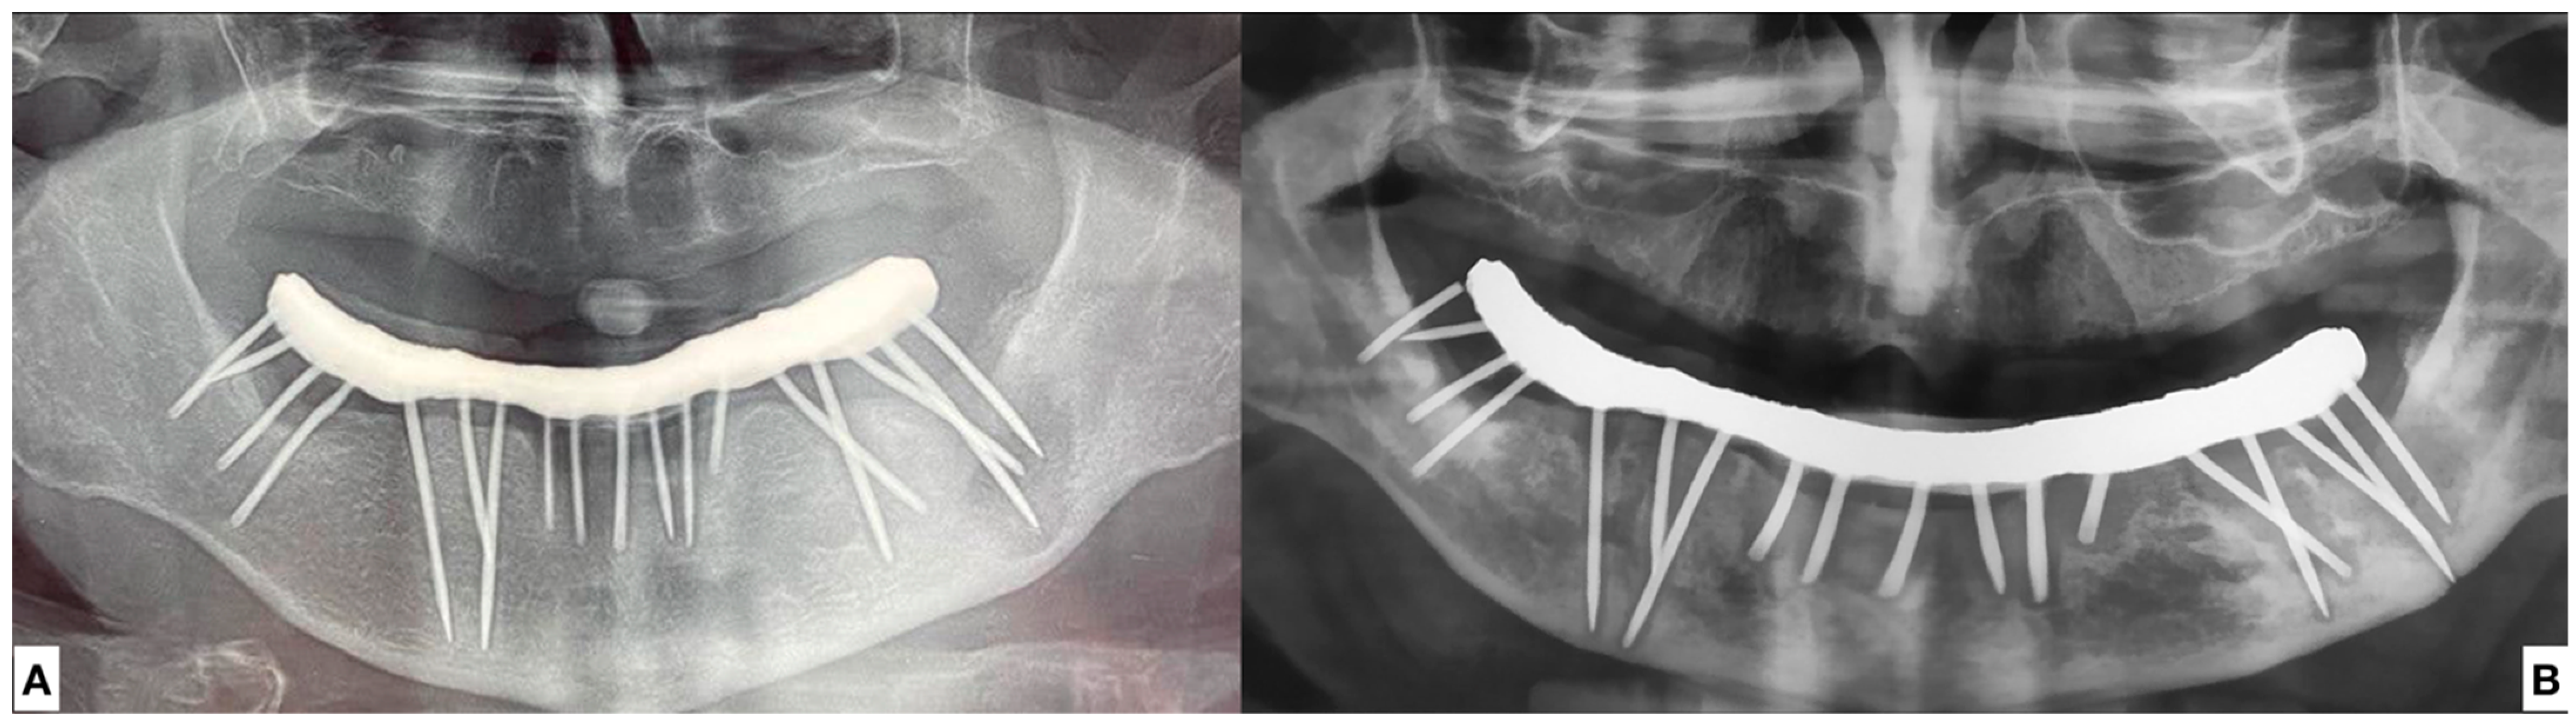

- The widespread and constant presence of infections of various sizes inside the mandible, presumably attributable to the endo-osseous presence of nails of unknown nature.

- Explantation of all the nails

- Platelet-Rich Growth Factors (PRGF) were inserted in the residual empty area left from the explantation of the nails and of the related infections.

2.1.1. Surgery Appointment (September 2021)

3.1. Case Report